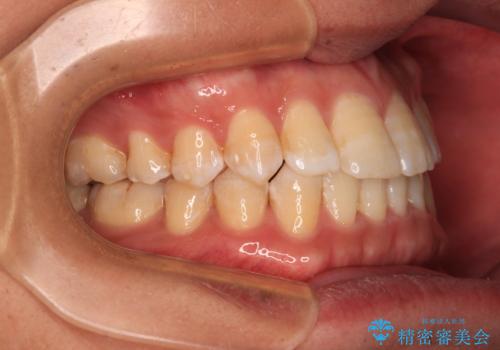

- 前歯のデコボコを気にして来院された患者様です。

インビザラインによるマウスピース矯正も適用となる歯列でしたが、できる限り自己管理の煩わしさのない状態で治したいとのことで、ワイヤー装置にて矯正治療を行うこととしました。

予定していた期間より長くかかりましたが、1年強できれいな歯列に仕上がりました。